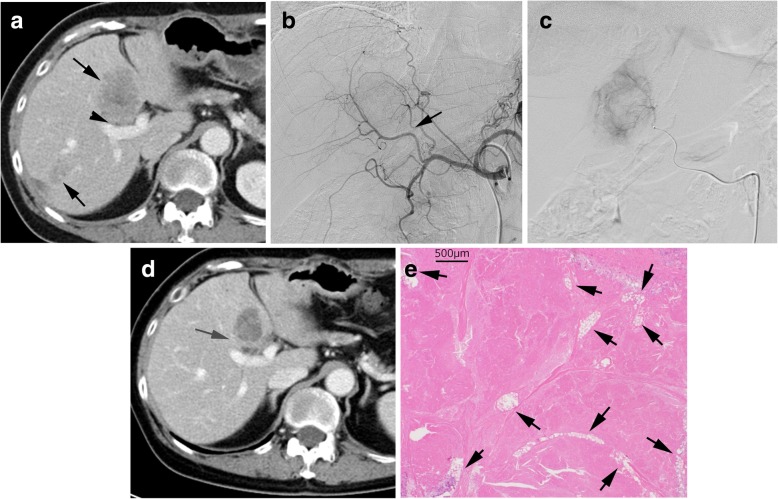

Fig. 3.

A case received curative surgical resection. This patient had 5 liver metastases, 4 in the left lobe and 1 in the right lobe. There was no extrahepatic metastasis. a. CT before TACE shows multiple liver metastases (arrows). A tumor in segment 4 was close to the portal vein (arrowhead). b. Hepatic arteriography; the tumor feeding artery was detected (arrow) by the angiography and TACE navigation system. c. A catheter was selectively inserted into the tumor feeding artery and 40 μm irinotecan loaded TANDEM was injected. d. CT after 3 cycles of the treatment of TACE and FOLFIRI showed the tumor shrunk and was separated from the portal vein (arrow). A bile duct adjacent to the portal vein was slightly dilated. e. Histological findings (Hematoxylin and eosin stain) of the resected tumor; almost the whole area of the tumor was necrotic and numerous 40 μm microspheres were seen inside the tumor (arrows)